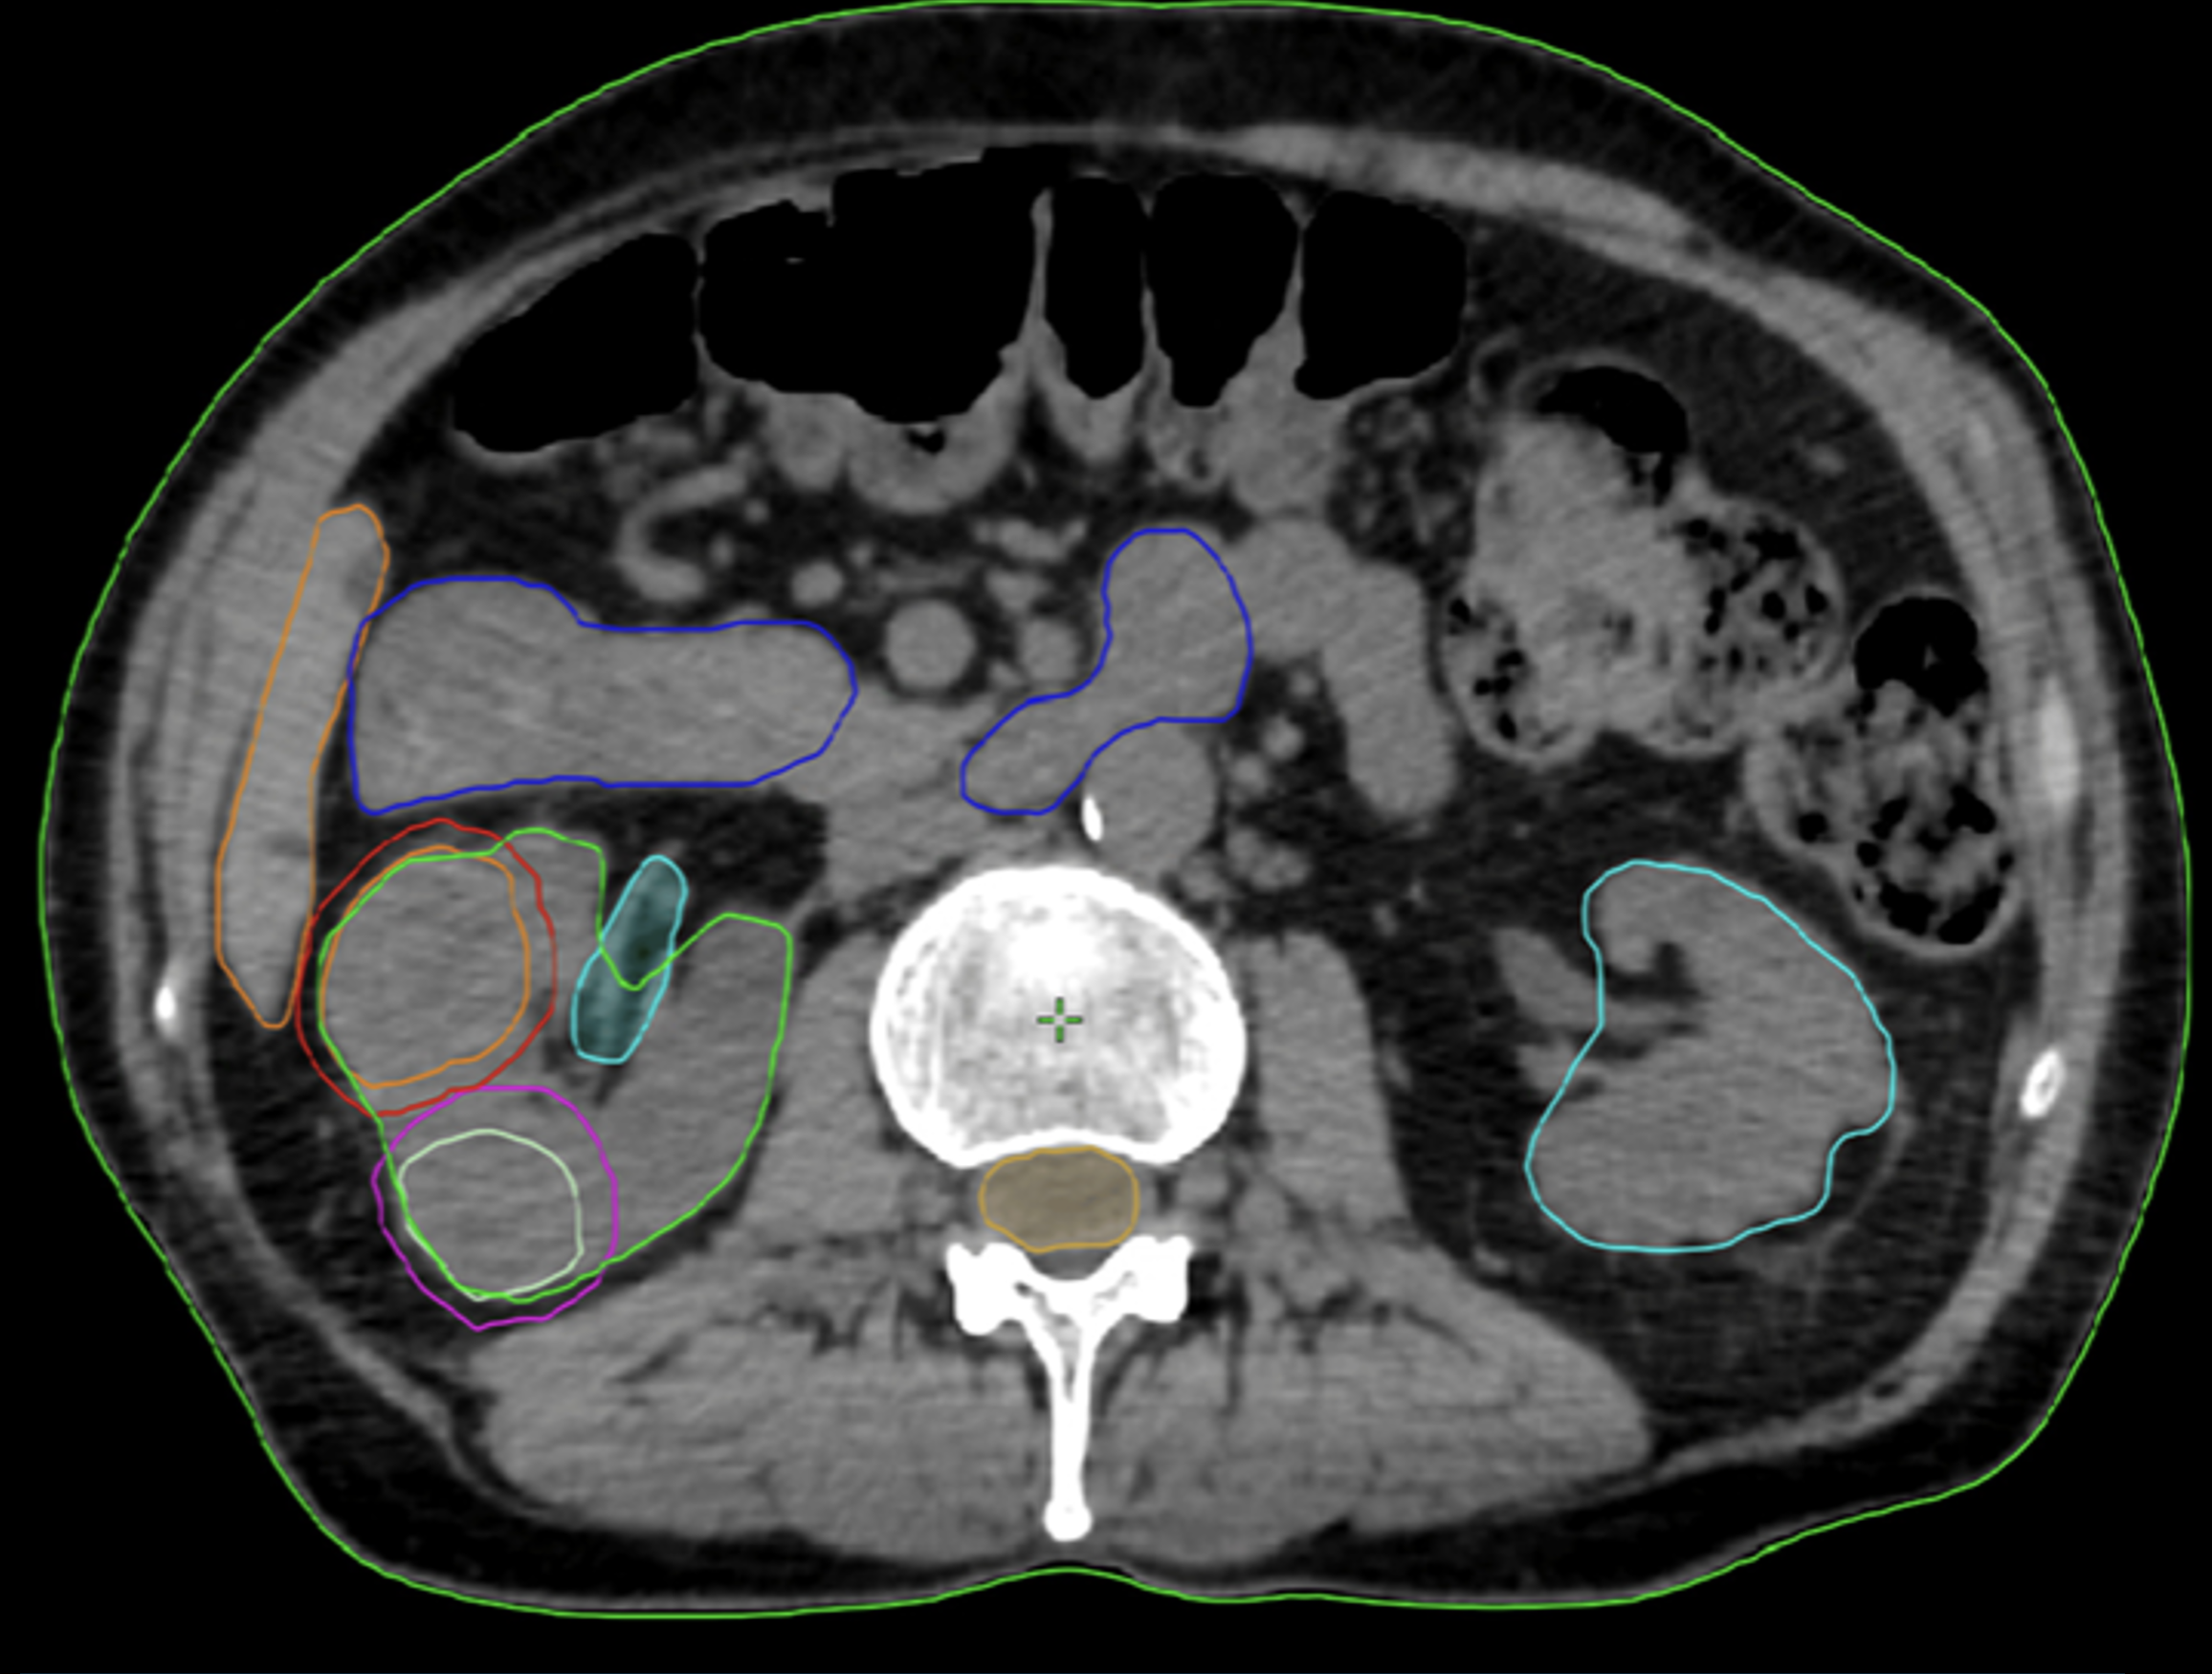

This retrospective study examines cancer control and health-related quality of life (HRQOL) outcomes in high-risk prostate cancer patients receiving robotic stereotactic body radiation therapy (SBRT) with Synchrony® real-time adaptive motion management.